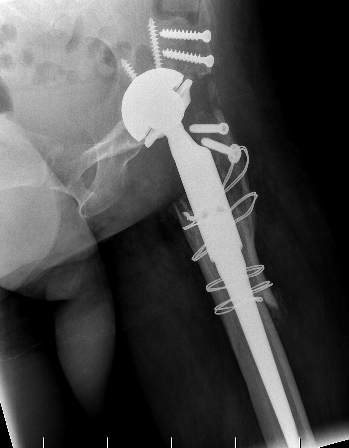

Conversion to THA

Hip fusion 1Hip fusion conversion 1Hip fusion conversion 2

www.boneschool.com/arthrodesis-conversion-THA